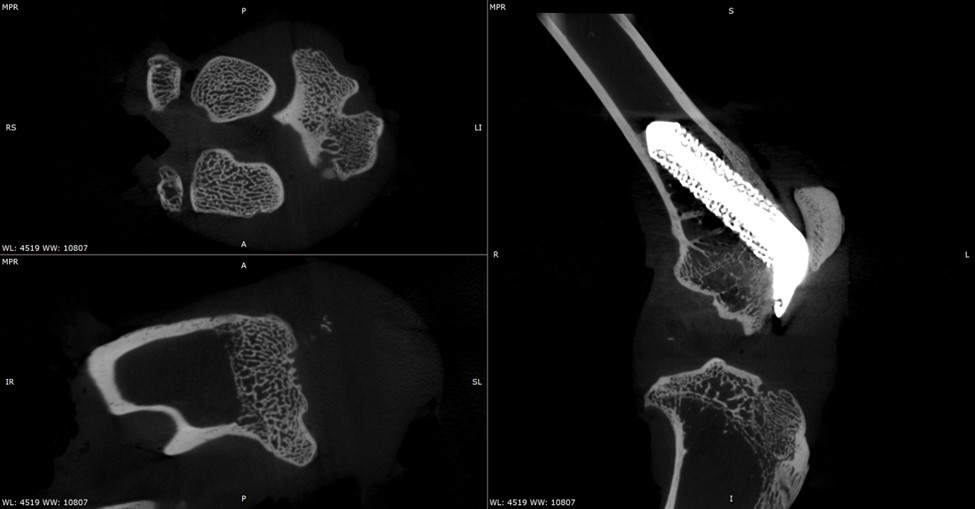

High‑resolution micro-CT enables the non‑destructive, 3D visualization of implants and surrounding bone over time. The images presented here showcase the use of micro-CT to study periprosthetic joint implantation and osseointegration in rabbit models, allowing tracking of implant positioning, bone remodeling, and early indicators of bone integration at multiple time points.

Below are micro-CT reconstructions of a femoral implant in a rabbit knee model. High-resolution imaging enables tracking of implant position and progressive changes at the implant-bone interface over time.

Micro-CT imaging allows repeated scanning of the same implanted joint, providing a powerful means to observe temporal changes in bone architecture without disrupting the tissue. These scans allow monitoring of how the surrounding trabecular and cortical bone adapts to the presence of the implant, capturing subtle changes in bone volume, density, and structure as healing progresses. This approach enables precise comparison of early versus later stages of implant integration within the rabbit knee.